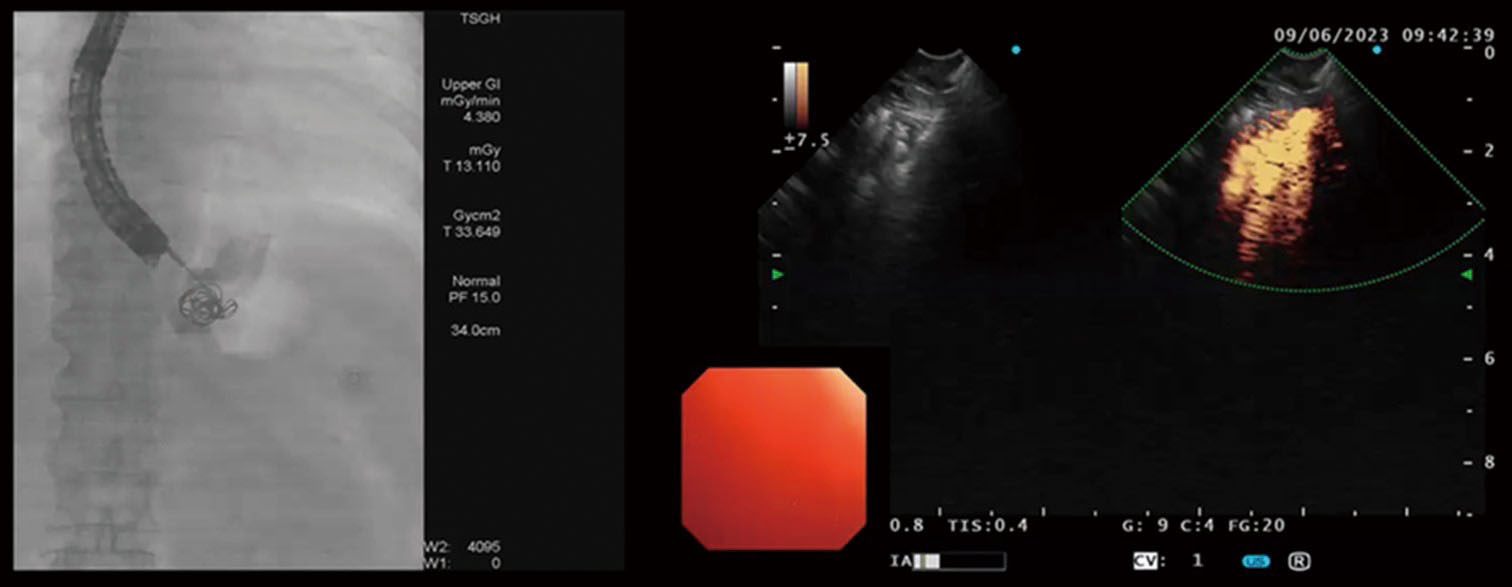

3. 內視鏡檢查:大腸鏡和胃鏡是確認潰瘍及採樣檢體的關鍵方式。

4. 影像學檢查:如核磁共振(MRI)之腸道攝影或電腦斷層(CT),可檢查克隆氏症好發影響之小腸腸段。